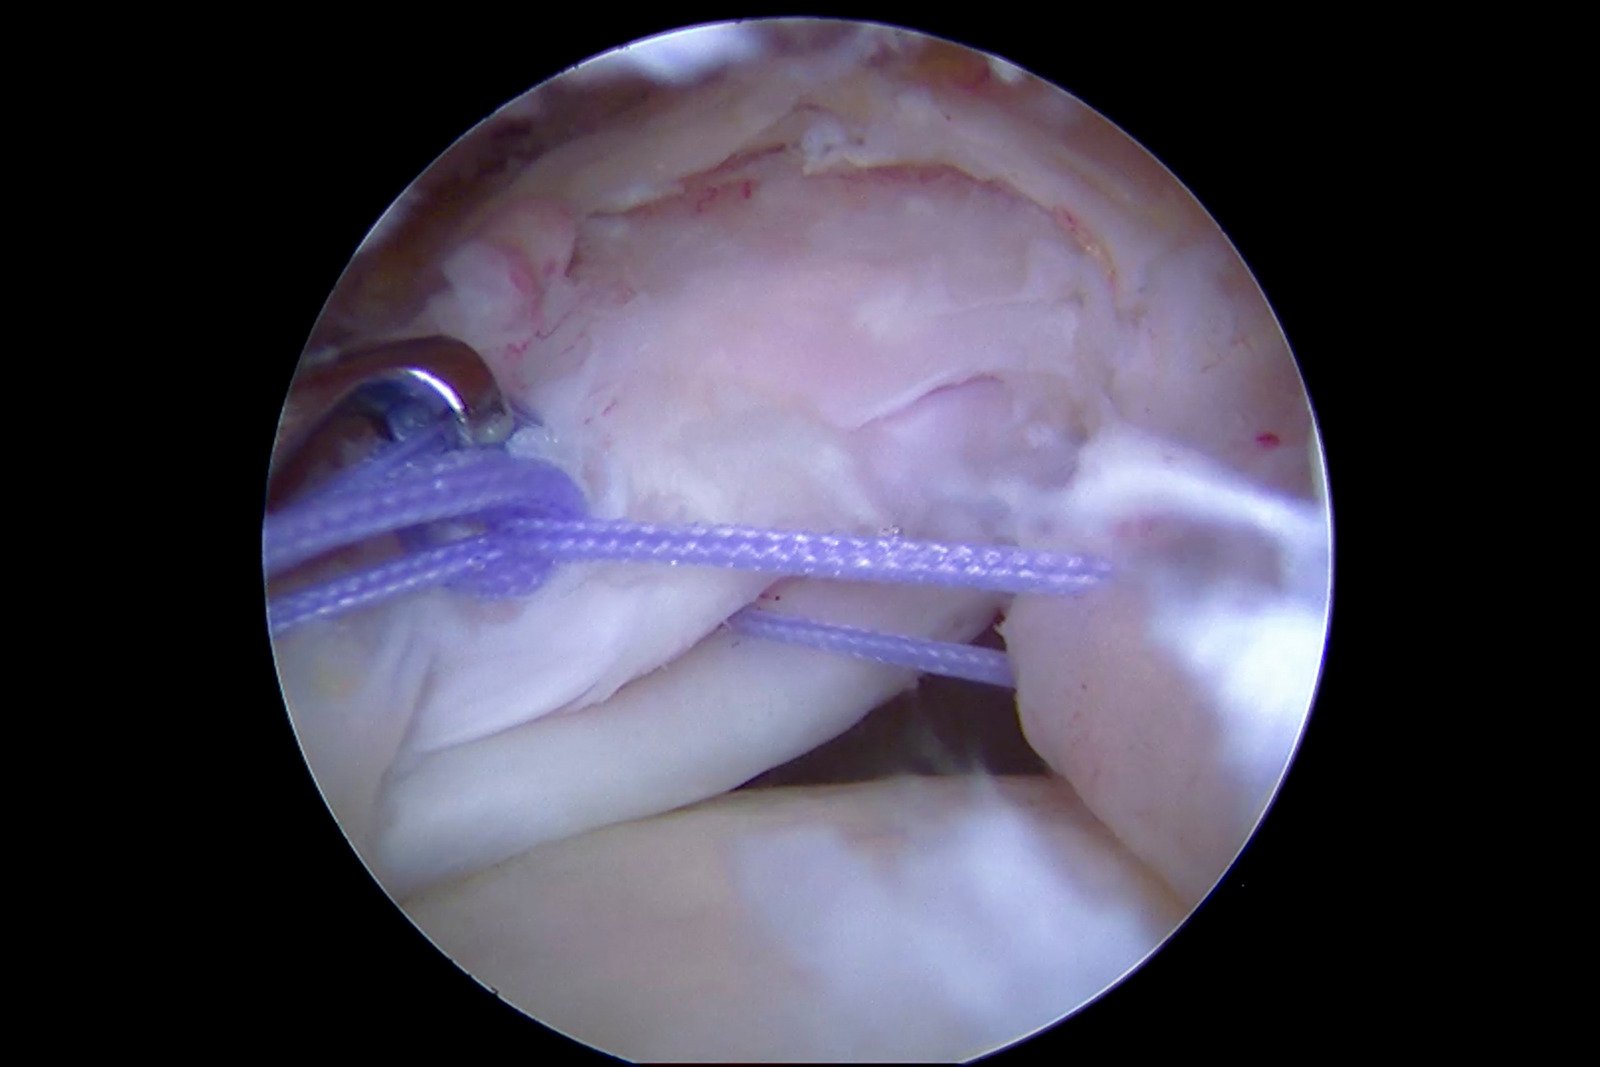

6. 힘줄 봉합 (Suture Technique)

봉합실을 특수 기구를 통해 파열된 힘줄에 통과

파열 형태에 따라 다양한 방법을 적용

단일열 봉합(single row repair): 앵커를 한 줄로 고정 → 소규모 파열

이중열 봉합(double row repair): 앞뒤 2줄로 고정 → 더 단단하고 재파열 방지 효과 높음

브리지 기법(suture bridge technique): 넓은 파열 시 넓은 면적에 힘줄 부착

봉합 완료 후 힘줄이 뼈에 단단히 붙었는지 확인